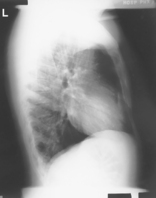

• Erect, on stretcher or in wheelchair

• Arms raised, crossed above head, or hold on to support bar

• Center thorax to CR, and to IR anteriorly and posteriorly

• No rotation or tilt, midsagittal plane parallel to IR, keep chin up